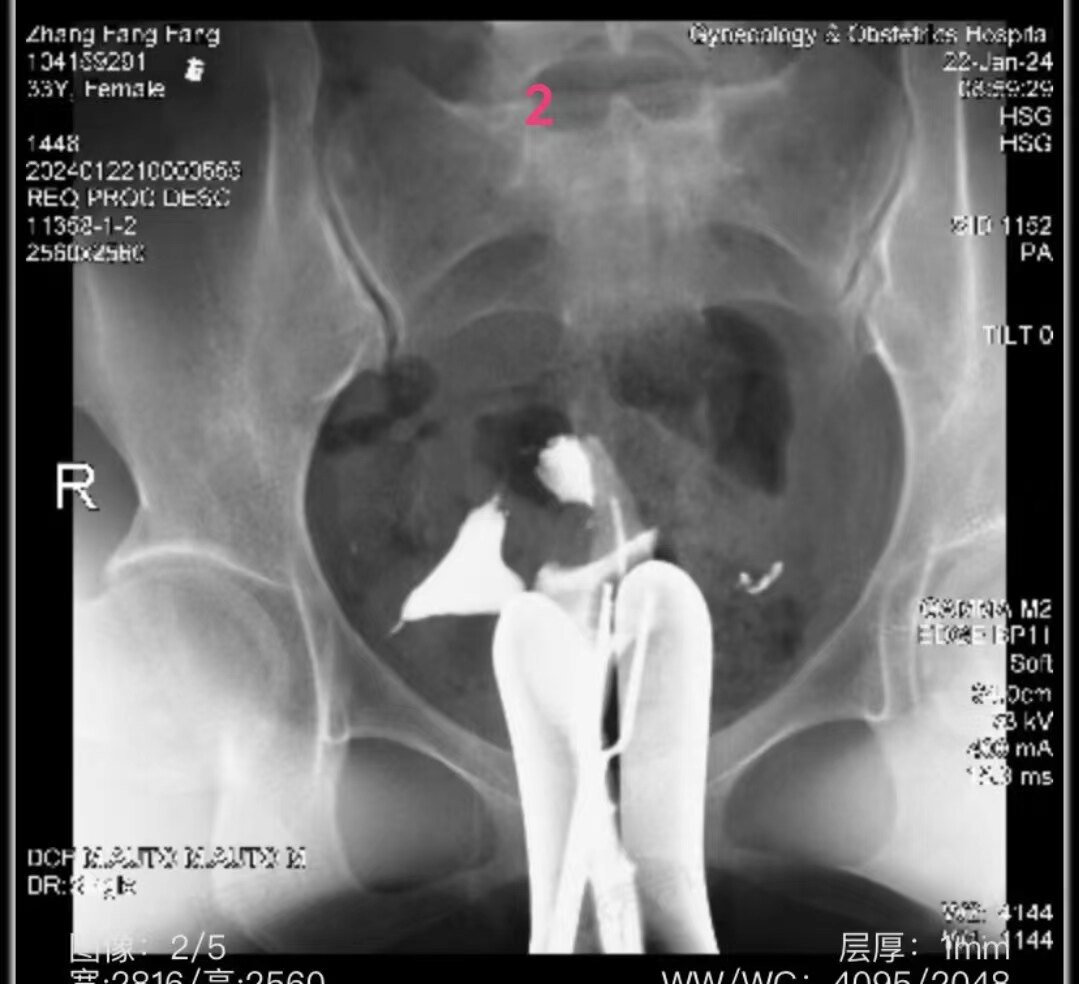

1.jpg

盆腔平片